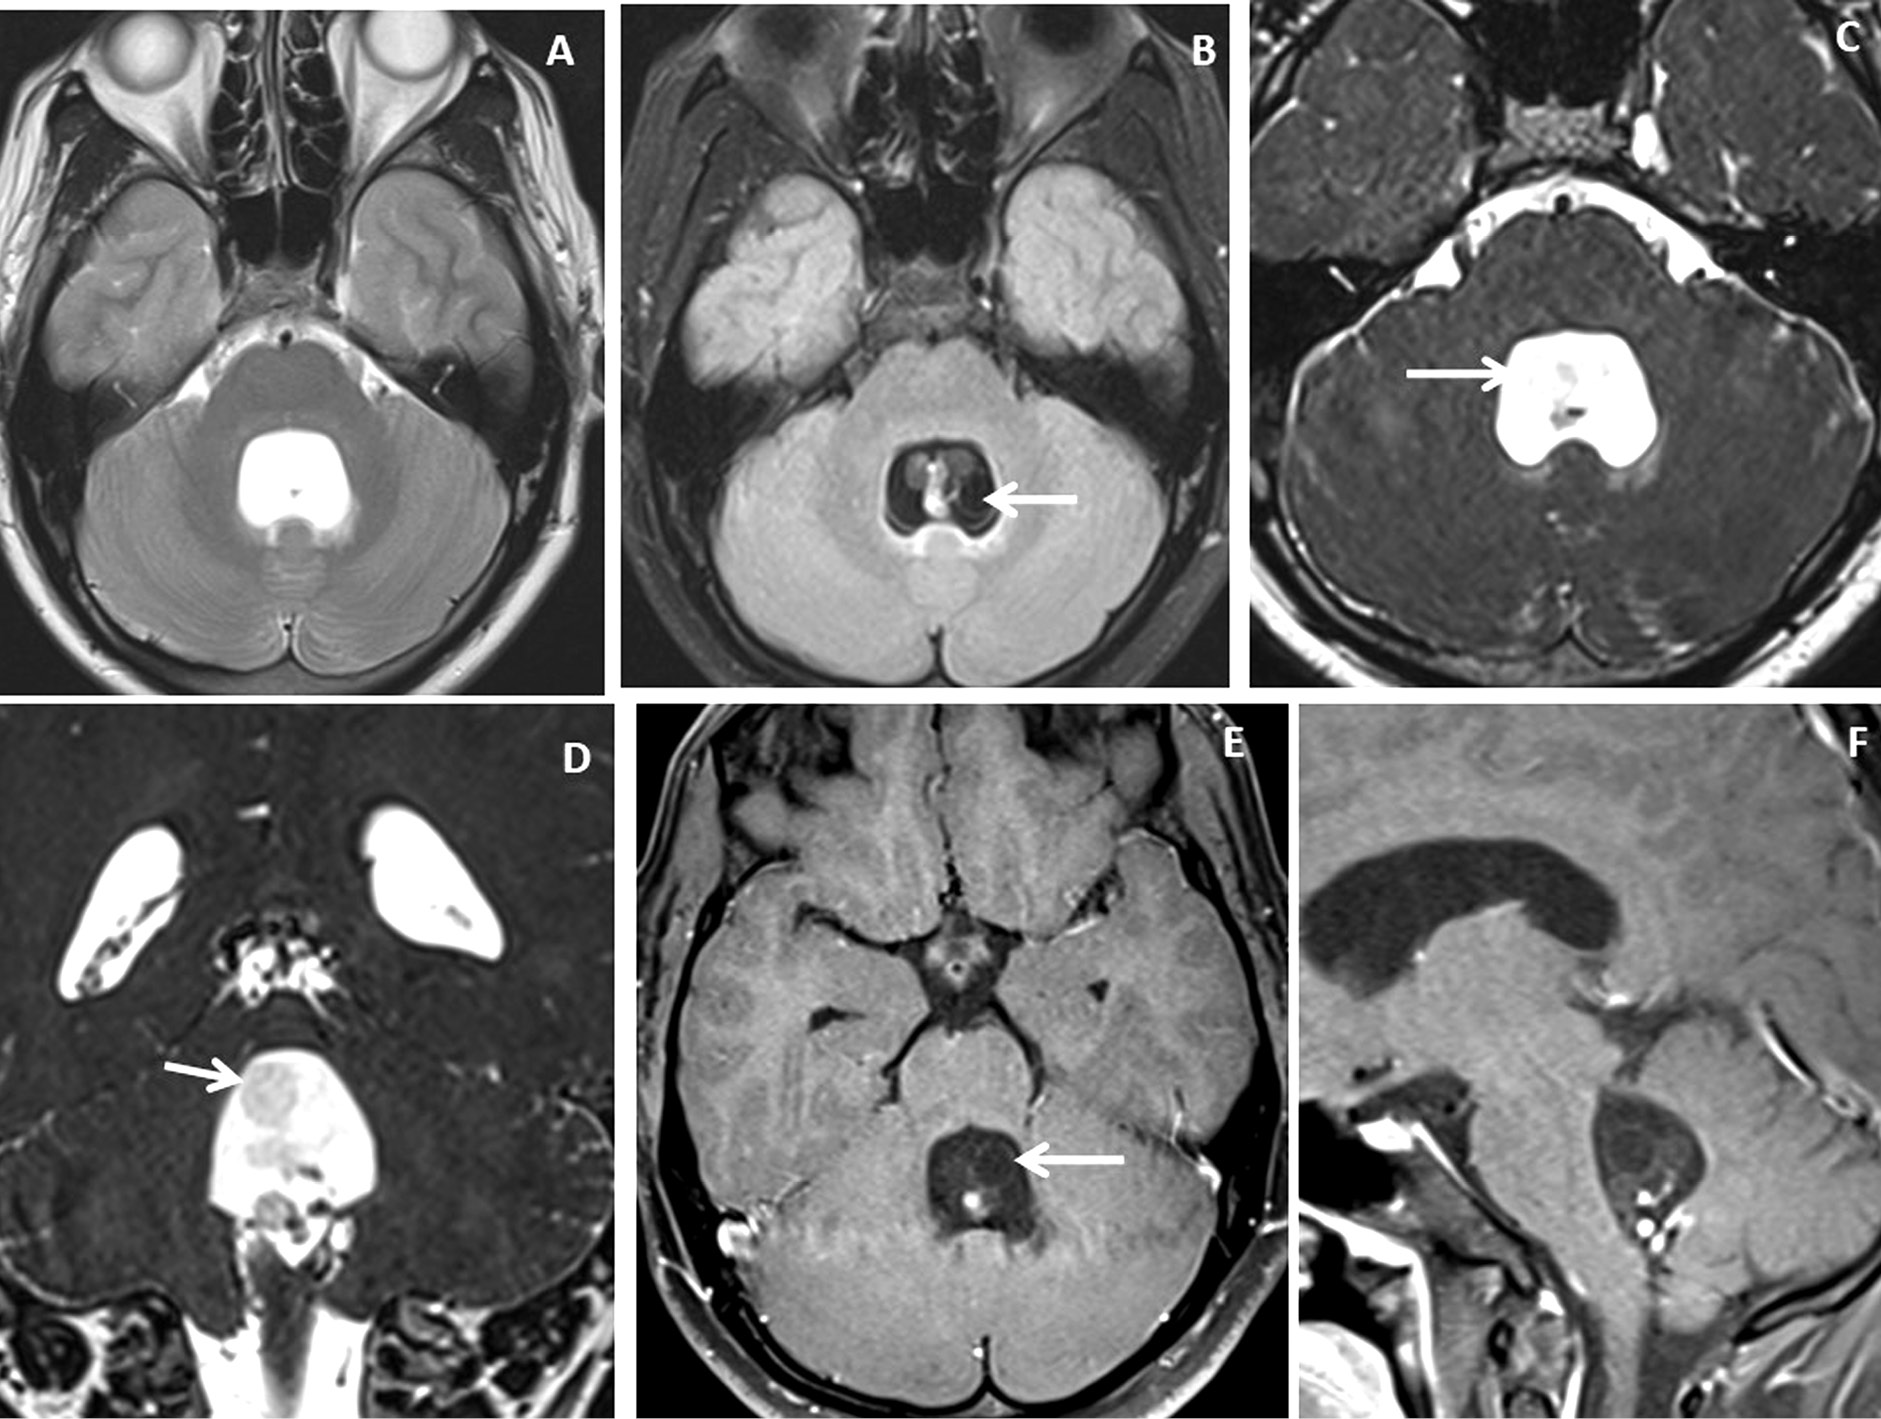

Figure 3. Brain magnetic resonance imaging of 25 years male with headache. (A-B) Axial T2WI and FLAIR images show distension and dilatation of the fourth ventricle with minimal periventricular CSF seepage. Variable signal intensity cystic lesions are seen within the fourth ventricle on the FLAIR image (arrow). (C-D) Axial and coronal heavily T2W images show multiple thin-walled hyperintense cystic lesions (arrows) with less hyperintense CSF signal within the 4th ventricle with variable sizes irregular nodules within. (E-F) Axial and sagittal T1W post-contrast image shows thin smooth enhancement of the intraventricular cyst (arrow) with enhancing irregular nodules. Post-contrast enhancement is also seen along the ependymal lining of the 4th ventricle, in posterior and inferior aspects.

Figure 4. Brain magnetic resonance imaging of 13 years male with severe headache, vomiting and acute neurological deterioration. (A-B) Axial T2WI images show marked distension and dilatation of the fourth ventricle with marked periventricular CSF seepage and supratentorial hydrocephalus. (C) Axial FLAIR image shows cystic lesions within the fourth ventricle (arrow). (D-E) Axial heavily T2W images show thin-walled hyperintense cystic lesions within the 4th ventricle with an oval to elongated appearing cystic lesion with scolex in the right foramen of Luschka (arrow). (F-H) Axial and sagittal T1W post-contrast image shows a thin peripheral enhancing cystic lesion with an irregular mural nodule in the right foramen of Luschka (arrow) and thin smooth enhancement of the intraventricular cysts. Nodular enhancement was seen in midline inferior margin of 4th ventricle near to foramen of Magendie (arrow).

Very thin smooth cyst wall enhancement was observed in 9(90%) patients (Figure 1 and 2) and irregular peripheral rim-like wall enhancement with an irregular nodule in 1(10%) patient. Ventricular ependymitis with smooth to irregular ependymal lining enhancement was observed in 7(70%) patients (Figure 3). Presence of hydrocephalus detected in 8(80%), where MRI revealed asymmetrical enlargement of lateral ventricle with periventricular CSF seepage in 4(40%) patients (Figure 1), dilatation of 3rd ventricle in 2(20%) patients and ballooned 4th ventricle in another 2(20%) patients(Figure 4).